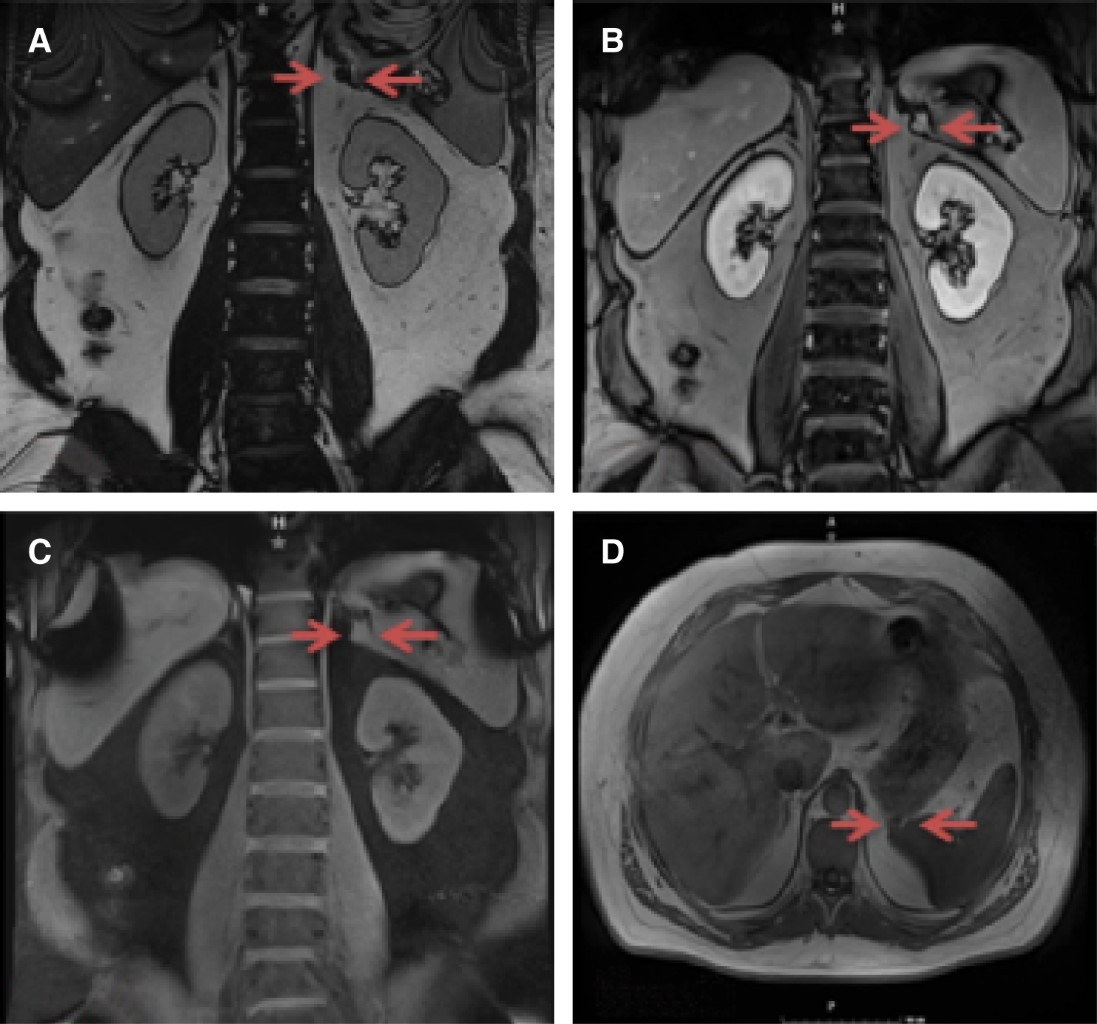

Introduction: ganglioneuroma is a rare benign tumor of neural crest origin arising from the sympathetic nervous system. The case presented reports the unusual clinical features and treatment options of retroperitoneal ganglioneuroma. Case report: a 36-year-old male with a history of chronic kidney disease secondary to difficult-to-control hypertension. Initial tests, including renal doppler ultrasound and I 131-MIBG scintigraphy were normal. A contrasted abdominal computed tomography scan was performed which demonstrated a 2 cm retroperitoneal mass adjacent to the left adrenal gland and further delineated by magnetic resonance imaging reporting probable paraganglioma. Plasma urine total metanephrine was significantly elevated. The patient was treated with preoperative alpha blockade, performing complete tumor resection laparoscopically. Histopathological examination reported the diagnosis of ganglioneuroma. There were no intra or postoperative complications, total hospital stay was two days and metanephrine levels normalized at follow-up. Conclusion: complete resection by laparoscopy is widely accepted as an adequate therapy without recurrence for the treatment of symptomatic retroperitoneal ganglioneuromas such as the clinical case reported, presenting a good prognosis.

Figure 1

Figure 2

Figure 3